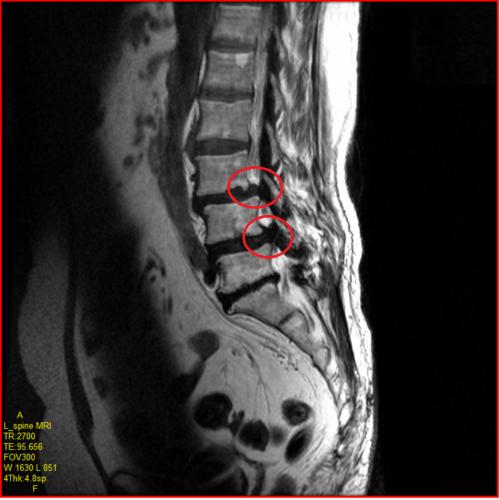

- MRI 검사: 척추관의 좁아짐, 디스크 돌출, 신경 압박 정도를 정확히 볼 수 있습니다. (가장 정확한 검사)